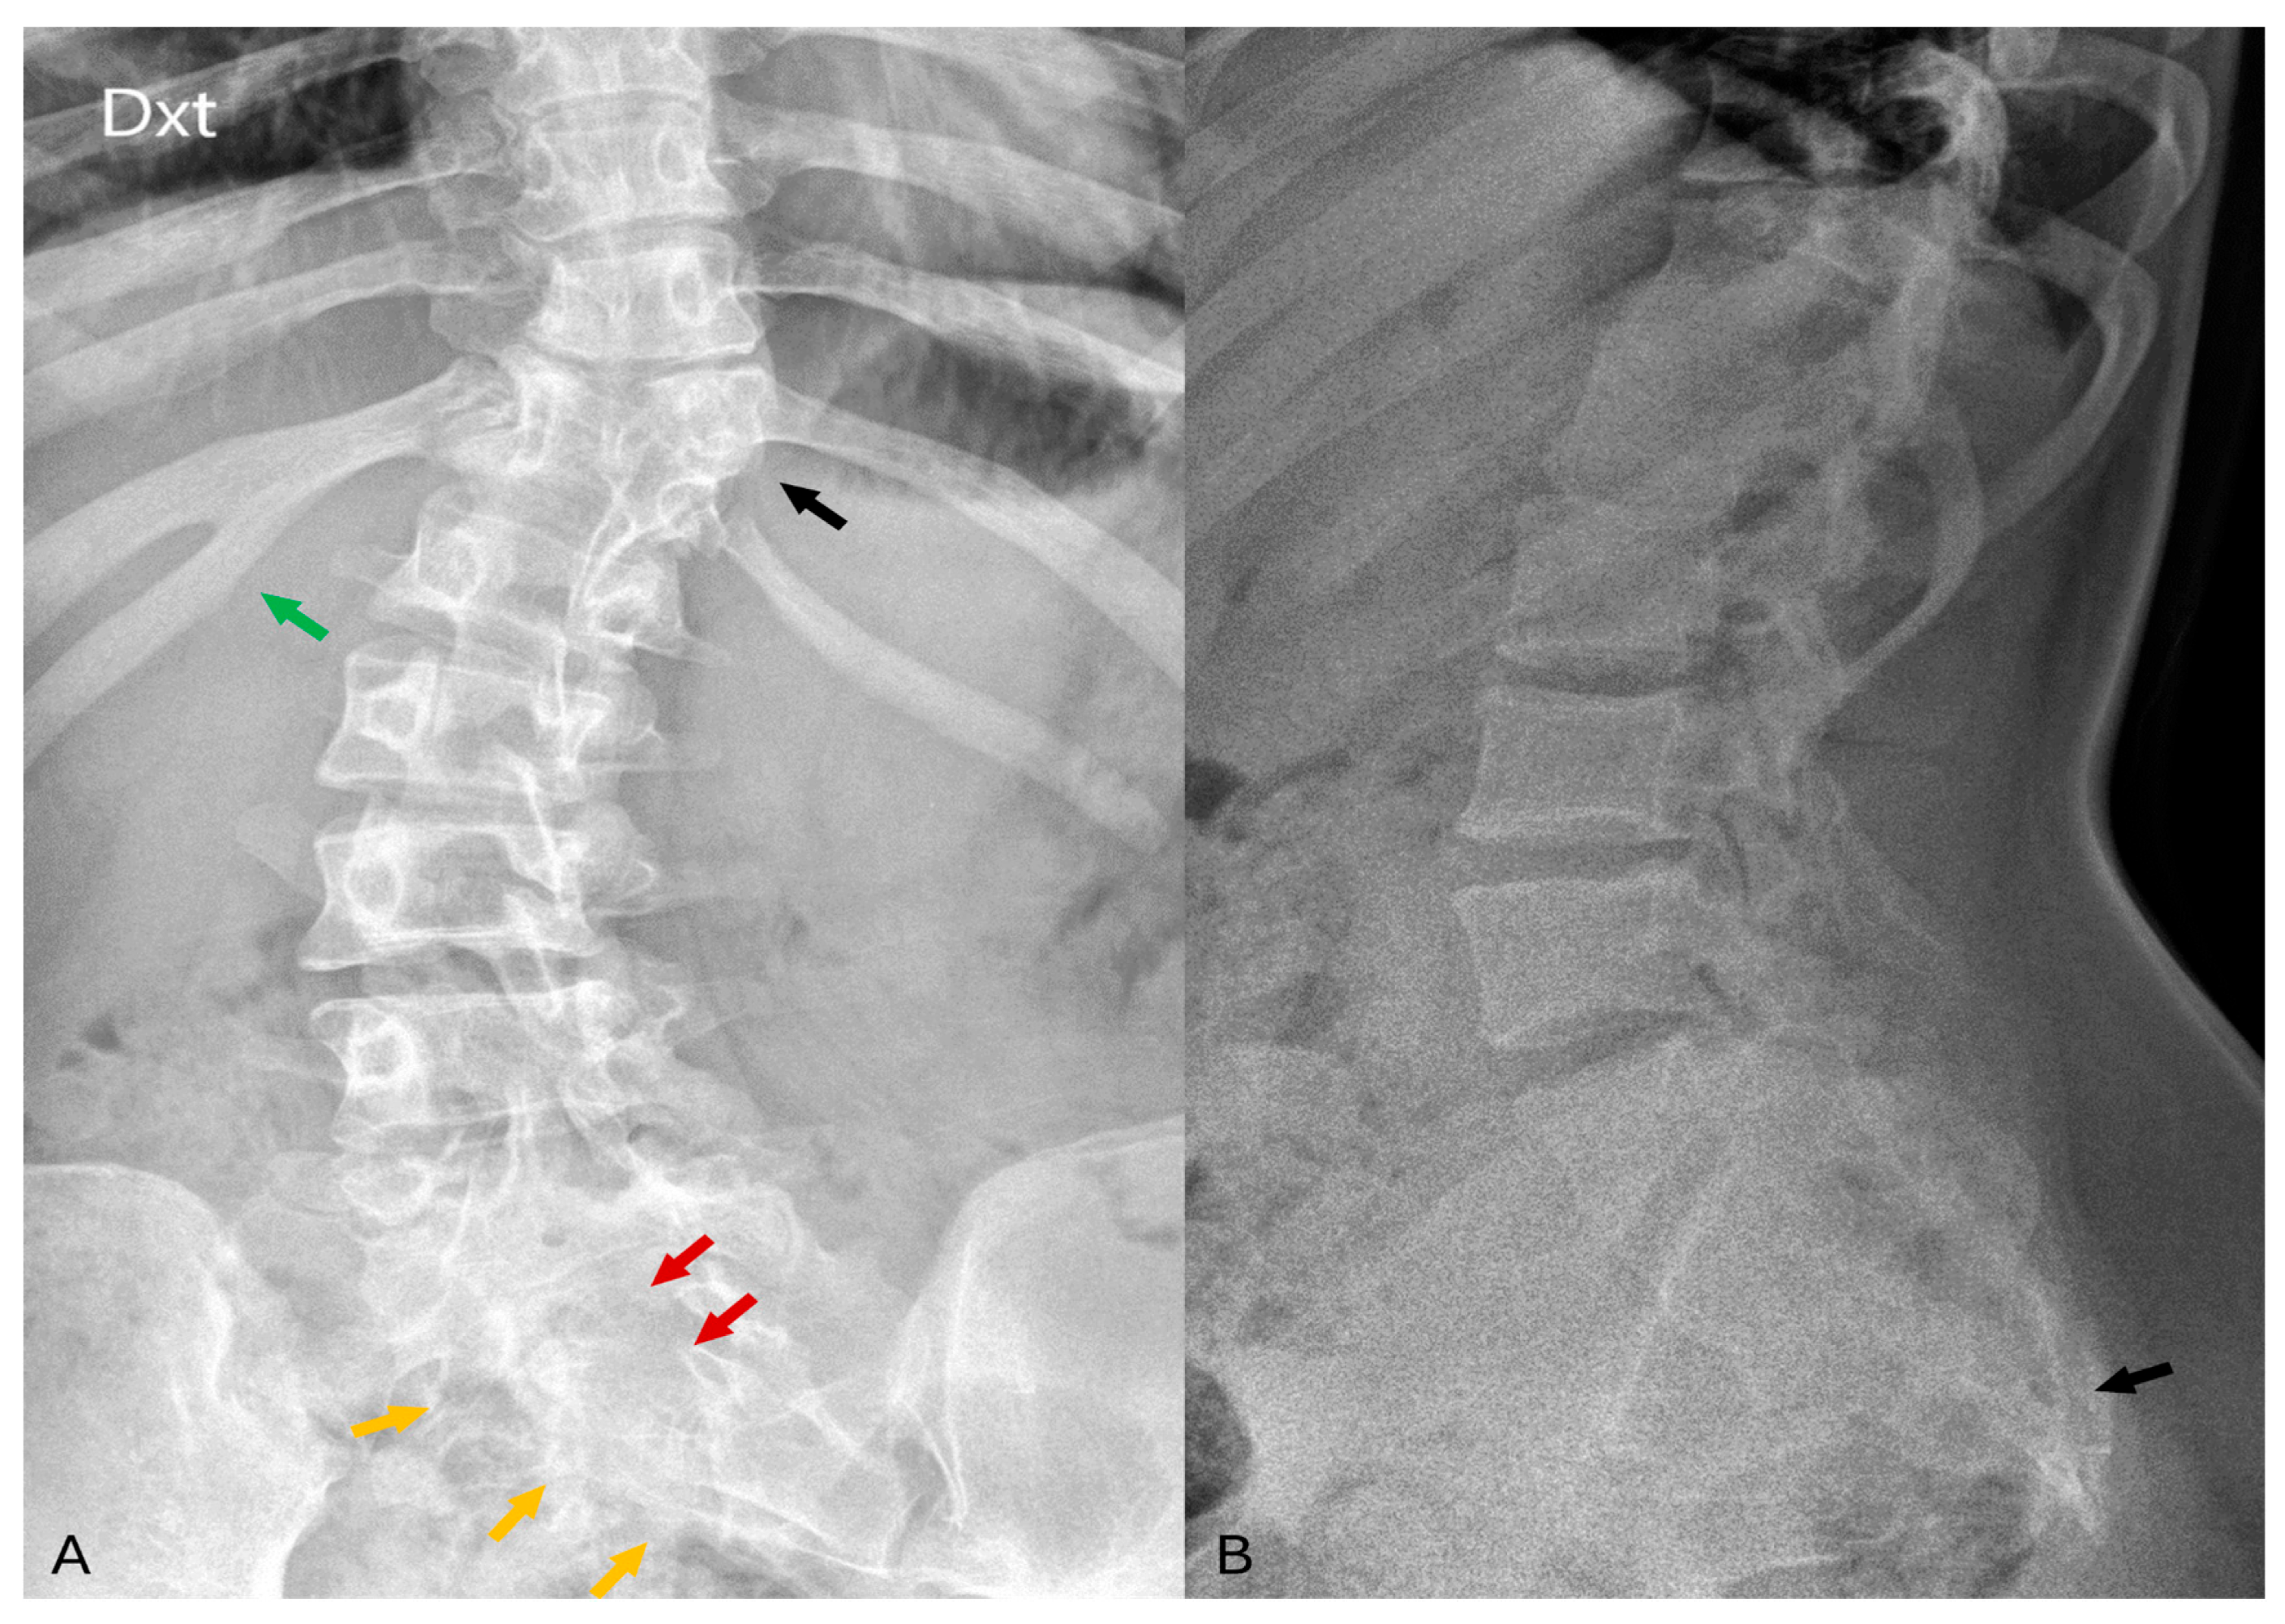

Figure 1.

(A) In the AP projection of the lumbar spine radiographs, notable findings include right-sided fusion of the 11th and 12th ribs (green arrow), partial segmentation of the 11th thoracic vertebra (black arrow), and posterior arch defects observed in the sacral vertebrae (red arrows). Suspicious structural changes in the right side of the sacrum can also be visible (orange arrows). (B) In the LL projection of the lumbar spine, visualization reveals a deformed and shortened sacrum as well as coccyx agenesis (black arrow).